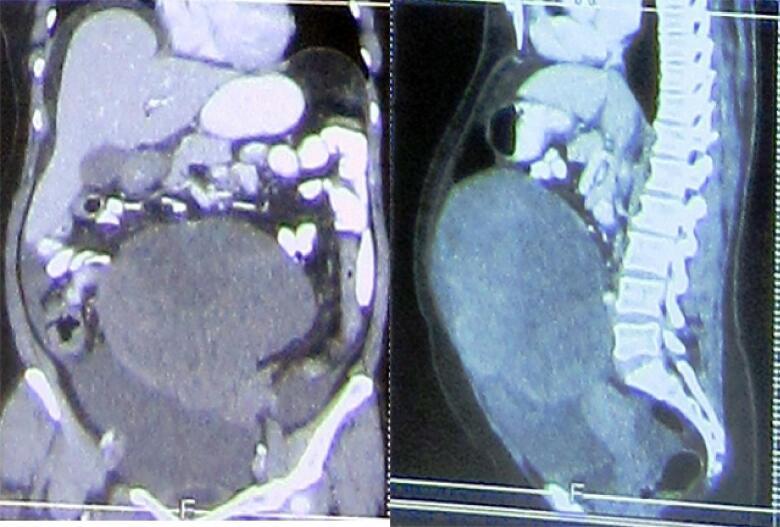

In this case study, we report a 52-year-old woman presenting with the chief complaint of unusual uterine bleeding. There was no specific finding in her past medical history. The CT study revealed enlarged bilateral ovary with a significantly large left ovarian mass and suspicious mass in uterus. By the diagnosis of ovarian mass, patient went under total abdominal hysterectomy with bilateral salpingo-oophorectomy (BSO), greater omentectomy, and appendectomy followed by post-op hormone therapy. Her follow-up was uneventful. The IHC and pathological study of samples revealed incidental LG-ESS uterus mass with metastasis to ovaries despite her primary diagnosis.

在本病例研究中,我们报告了一名52岁女性,主要主诉为异常子宫出血。她既往病史无特殊发现。CT检查显示双侧卵巢增大,左侧卵巢有一个明显较大的肿块,子宫内有可疑肿块。通过卵巢肿块诊断,患者接受了全腹子宫切除术、双侧输卵管卵巢切除术(BSO)、大网膜切除术和阑尾切除术,随后进行术后激素治疗。她的随访情况良好。样本的免疫组化(IHC)和病理研究显示,尽管她最初的诊断并非如此,但偶然发现子宫肿块为LG-ESS并伴有卵巢转移。